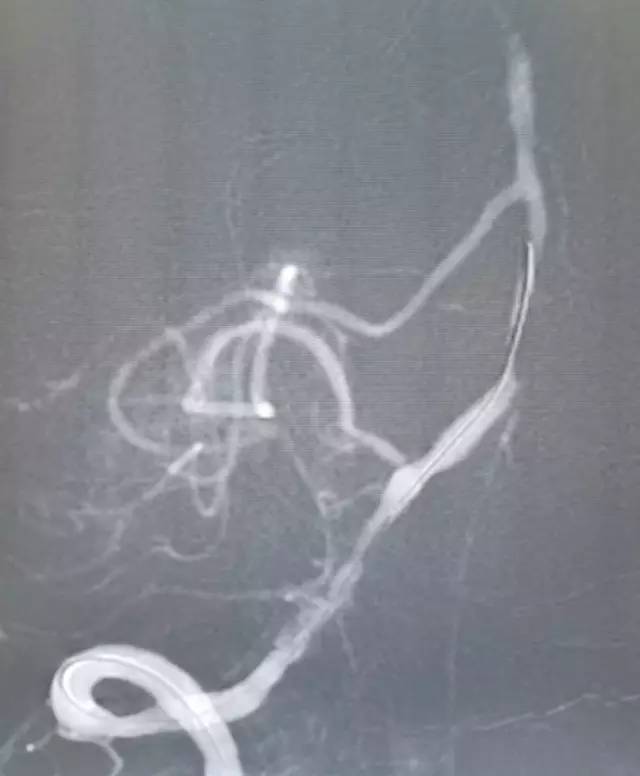

经微导管送入Transend(0.014” ,300cm)微导丝至基底动脉中段。撤出微导管沿微导丝送入Sprinter Legend RX球囊(2.0mm×15mm)准确定位于病变处预扩张,扩张后造影显示,前向血流改善,残余狭窄50%(图10)。

图10

撤出球囊导管,沿Transend微导丝送入XT-27微导管,撤出微导丝后沿微导管送入Neuroform EZ(3.0 mm×30mm)自膨式支架至病变处释放,造影显示前向血流好,TICI分级 3级,残余狭窄率约10%,同侧PICA显影良好(图11)。观察10分钟无变化后结束治疗。

图11